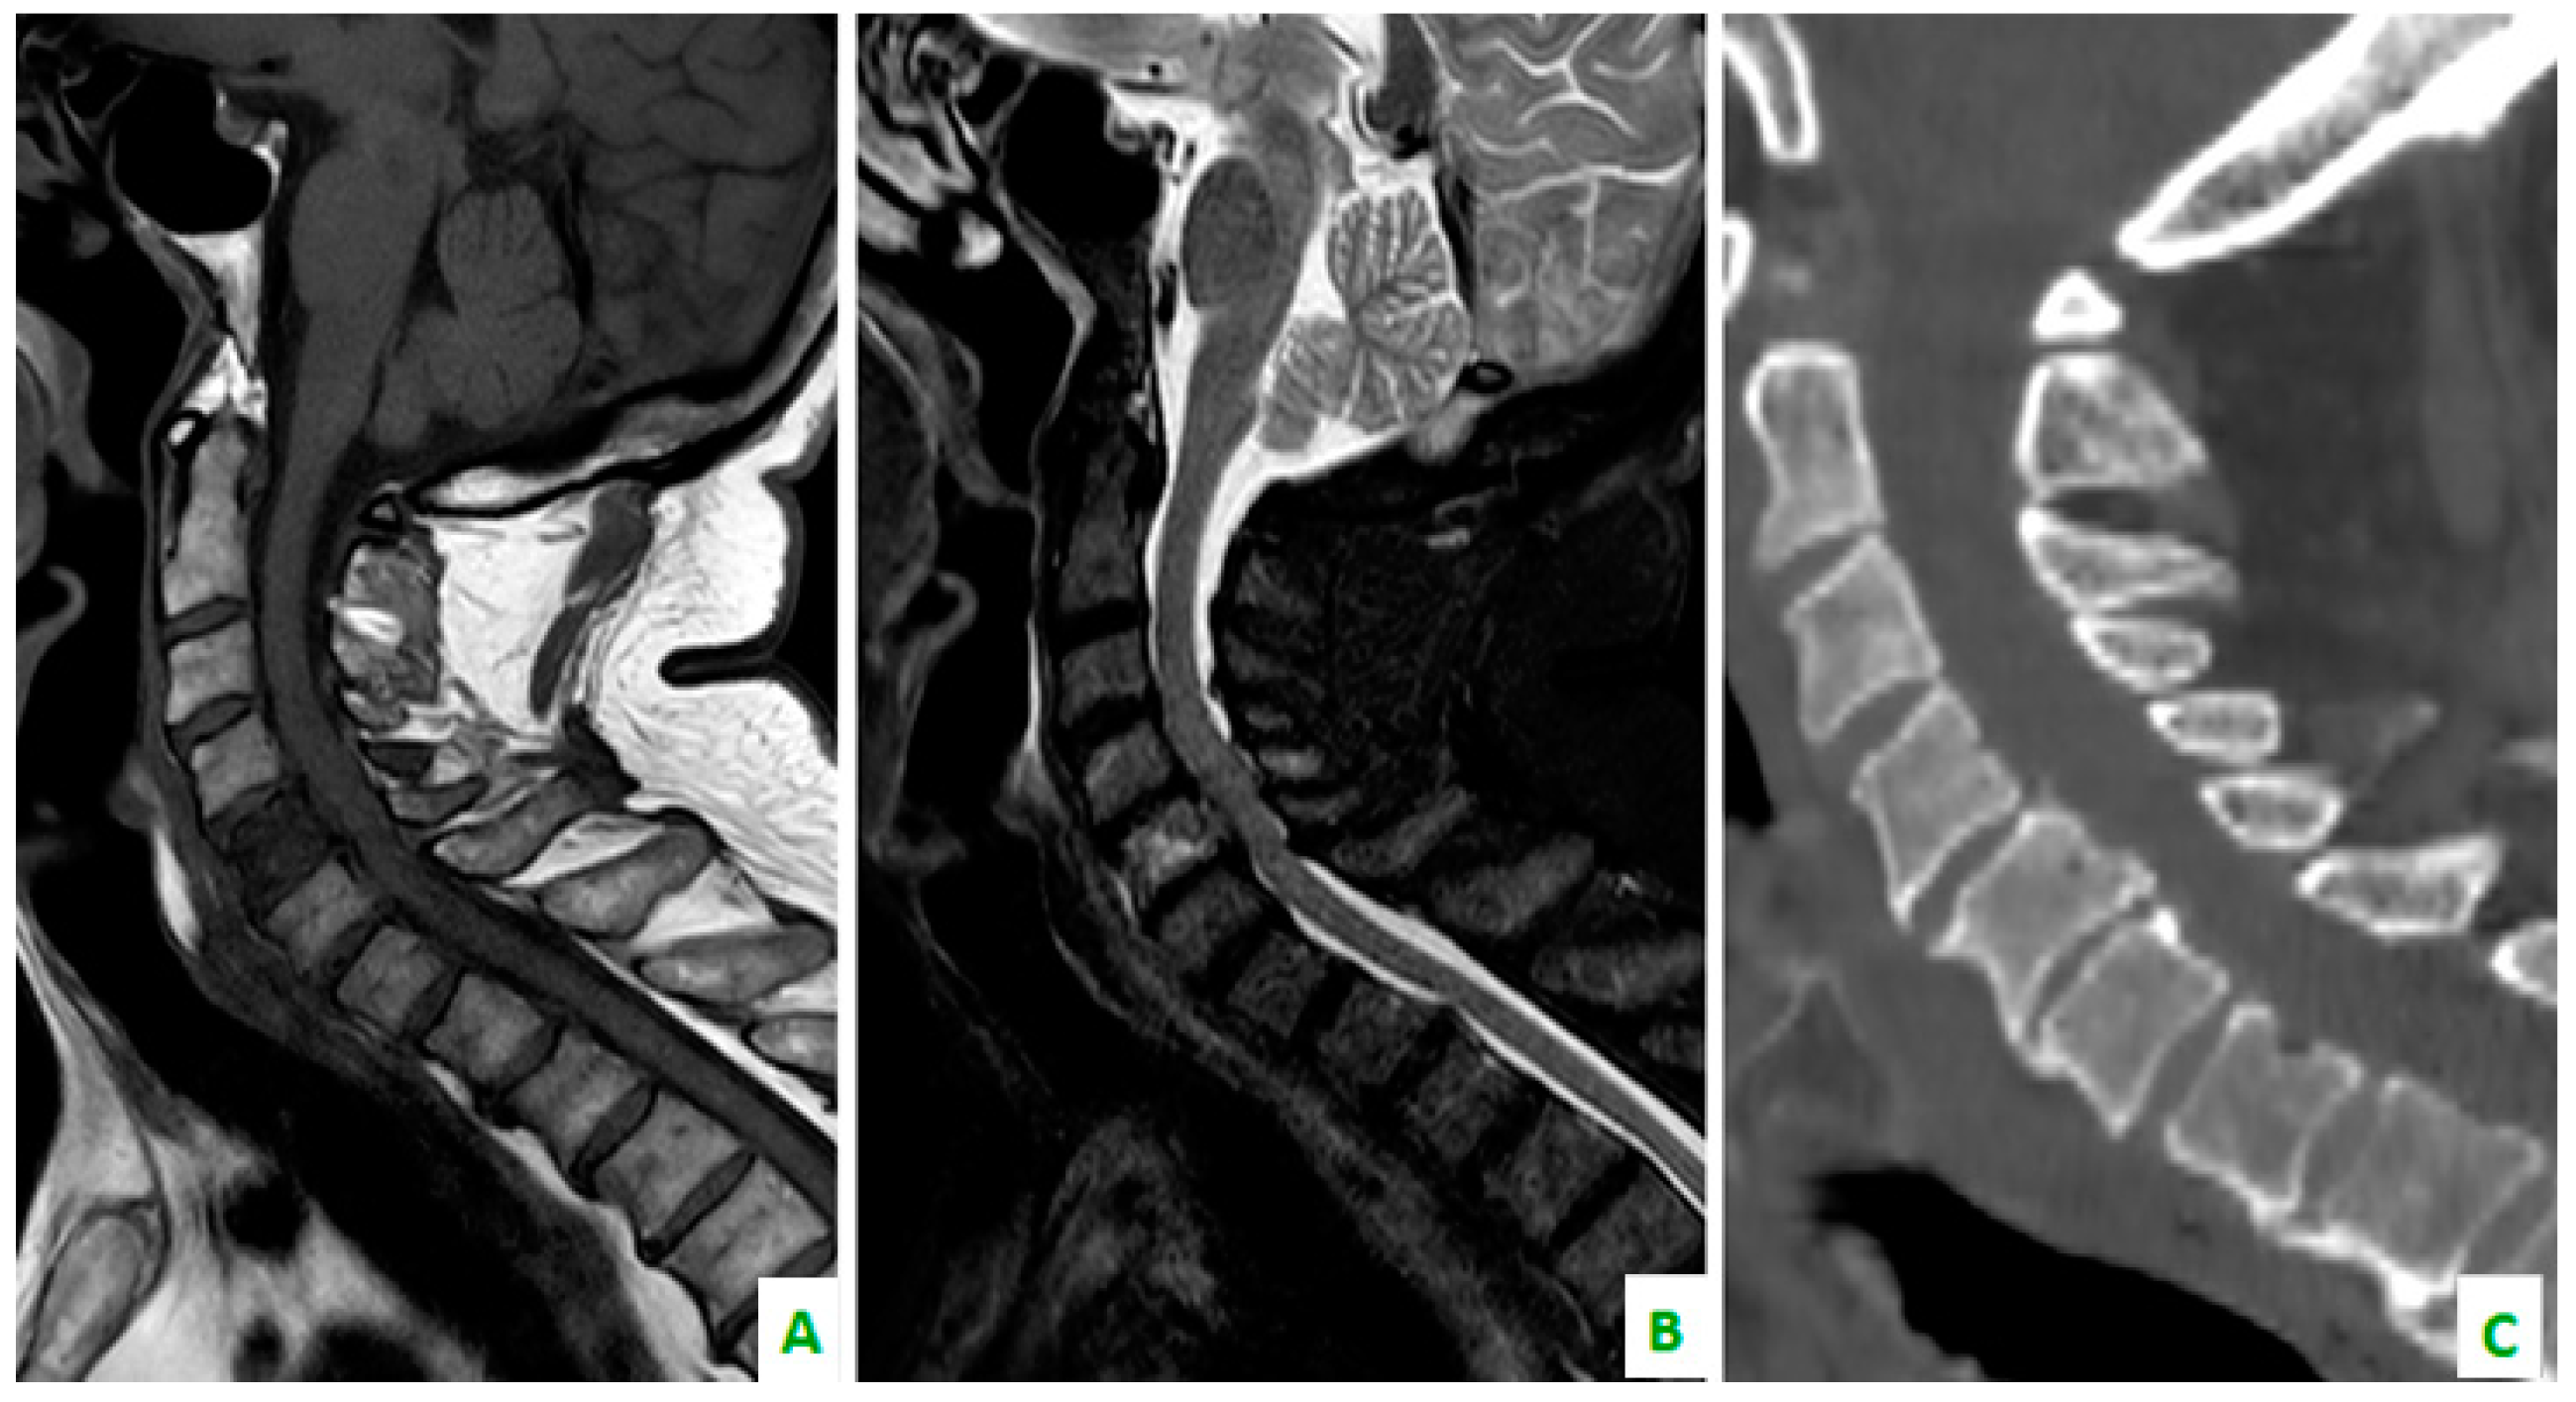

Figure 5. (A) A T1 sequence and (B) STIR sequence, performed with a dedicated spinal MRI, highlight the lung metastases. (C) Cervical spine on a sagittal reconstruction of a computed tomography (CT). The bone metastasis is not so clear.